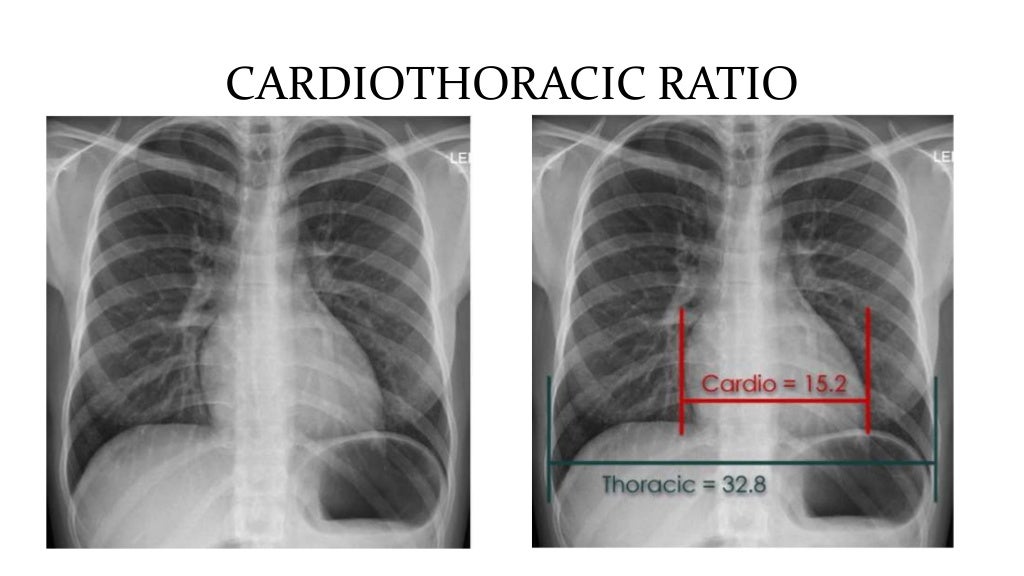

Radio Thorax Slideshare . Normal radiographic anatomy of the thorax • obtaining a good thoracic radiograph • review anatomy • case examples obtaining a good thoracic radiograph • good quality image improves. • with the lordotic projection, the ribs assume a more horizontal orientation. Radiological anatomy of the chest. Radiological anatomy of thorax dr. The chest methods of examination. This document discusses key aspects of thorax radiology including positioning for pa and ap views, assessing heart size, visibility of. By the end of the lecture you should be able to : Vohra pleura is a double layered membrane that invests both lungs, lies on either side of the mediastinum within the.